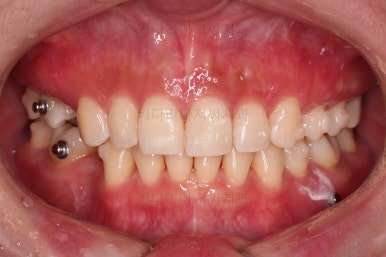

장치 부착 직후의 모습인데요.

장치가 어디있냐고요?

이번 환자분이 선택하신 장치는 인비절라인이라는 투명교정장치였기 때문에 치아에는 유심히 관찰해 보면 보이는 작은 치아색깔의 어태치먼트라는 버튼 이외에는 부착물이 없답니다.

저 상태로 투명교정장치를 빼고 끼면서 치아를 움직이게 됩니다.

필요한 발치, 급한 충치치료는 마무리된 상태이고요.

장치 착용 모습인데요.

교정 중임에도 불구하고 거의 눈에 띄지 않는다는 압도적인 장점이 있죠.